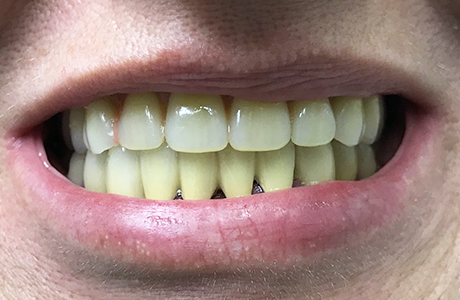

До и после лечения

Пациентка обратилась в «Стоматологию Комфорта» с жалобой на отсутствие зубов верхней челюсти. По результатам обследования врач стоматолог-ортопед, хирург-имплантолог Мельников Алексей Владимирович назначил имплантацию по методу «all-on-4». По истечении 6 месяцев после операции проведено обслуживание условно-съёмного протеза. Также врач начал восстановление нижней челюсти коронками в комбинации с бюгельный протезом.

Имплантация по методу «all-on-4» позволяет восстановить эстетику улыбки при отсутствии большей части зубов или нецелесообразности лечения имеющихся зубных единиц. При этом метод «all-on-4» в плане расходов является более выгодным для пациента, чем восстановление отдельных зубов.